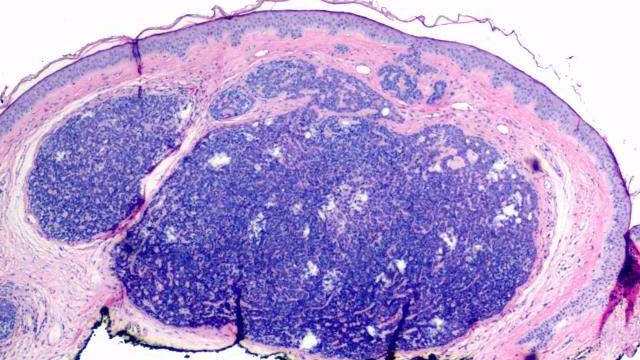

(双侧卵巢)交界性浆液性乳头状肿瘤_医学

图片尺寸960x720